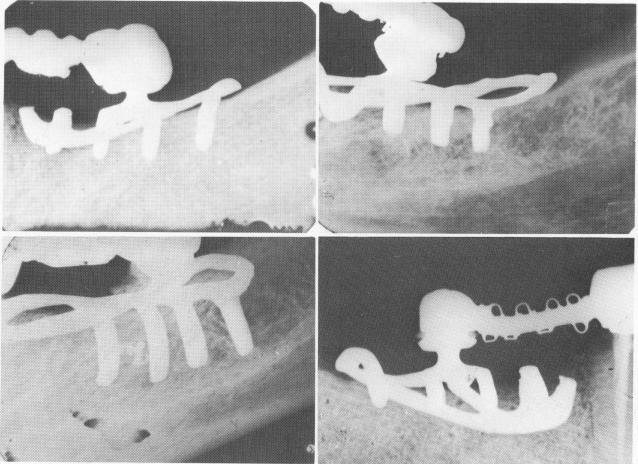

Fig. 12-99. Periapical intraoral x-rays of five different cases utilizing the unilateral subperiosteal implant as the posterior abutments. These cases with the lingual fingers have been in the mouths of these patients from 7 to 12 years. A shows a 12-year postoperative radio-graph.